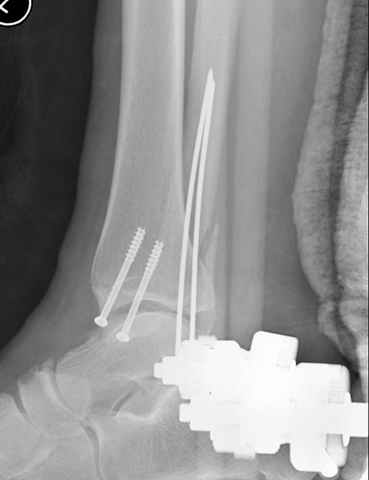

Я вот все в толк не возьму смысл отдельной фиксации малоберцовой кости пластинкой, если все равно будет аппарат с фиксацией стопы, т.е. возможностью провести спицы в пятку, таран, наружную лодыжку и еще черт-те куда. Остеосинтез пластинкой выглядит логичным в случае, когда наружная фиксация планируется как временная. Но тут-то аппарат будет окончательным фиксатором.

Еще, кстати, о фиксации лодыжки, если уж непременно хочется ее отдельно стабилизировать - при таком характере перелома замечательно должен сработать предложенный проф. Лазаревым с соратниками способ фиксации напряженной V-образной спицей. Опять же, открытая репозиция не нужна, мы делаем непрямую репозицию именно аппаратом. В приложении пример, там перелом малоберцовой куда менее поперечный, чем в данном случае, но все равно получилось закрыто без пластинки.

I can't realize why plate fibula separately if anyway external fixator including the foot is planned, i.e. one may insert wires to the talus, calcaneus, lateral malleolus and anywhere else. Plating looks reasonable if only temporary ex-fix is planned, but in the case it will be definitive.

A propos fibular fixation if one is eager to stabilize it separately. In the fracture pattern a way of closed fixation by V-shaped stressed wire (advanced by colleagues from Moscow, prof. Lazarev A.F. et al.) must be excellent. We use indirect closed reduction by the external fixator. Example attached, that fibular fracture is even more suitable for plating but the wire did the job.